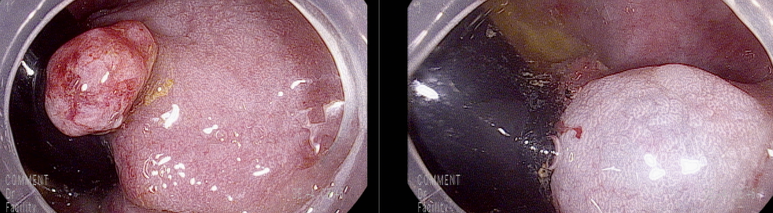

항문연 경계에 아래와 같은 13 mm 크기의 경이 있는 용종

표면에 발적변화를 보았을 때 마찰에 의한 출혈점 가능성